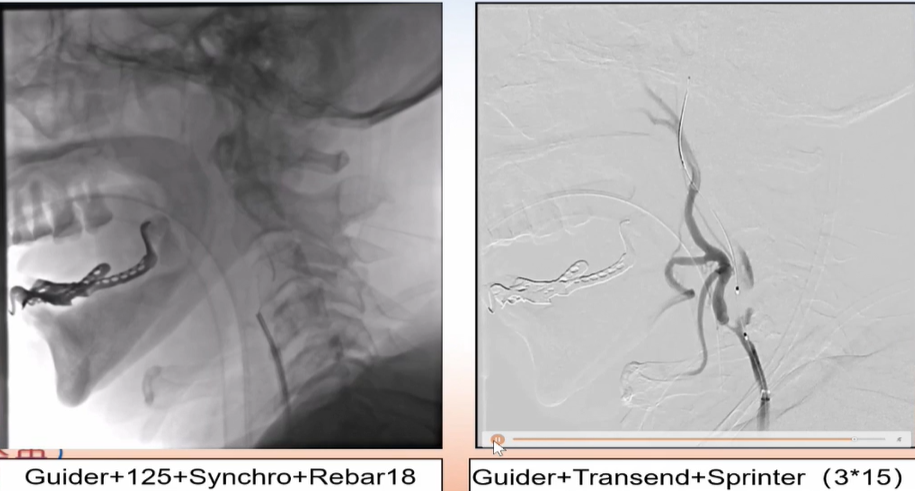

手术过程

在Synchro微导丝与Rebar-18支架导管的辅助下顺利超选上去,借助Transend导丝使用球囊穿梭技术将Sprinter(3*15)球囊装入血管真腔中。

过程影像

病历夹什么径技·第152期|串联营病历夹:川陕大营_https://www.jmylbn.com_新闻资讯_第83张

病历夹什么径技·第152期|串联营病历夹:川陕大营_https://www.jmylbn.com_新闻资讯_第84张

<<滑动查看下一张图片>>

由于guiding通过失败所以先处理近端,将Spider FX(5)保护伞置入进行了远端保护,近端放置了WALLSTENT支架,然后收伞,顺势将guider通过,结果其无法到达远端。

病历夹什么径技·第152期|串联营病历夹:川陕大营_https://www.jmylbn.com_新闻资讯_第85张

病历夹什么径技·第152期|串联营病历夹:川陕大营_https://www.jmylbn.com_新闻资讯_第86张

狭窄段用四个球囊后扩张,将cat6推过狭窄段,发现可能存在远端栓塞,因此将guider退了一下。